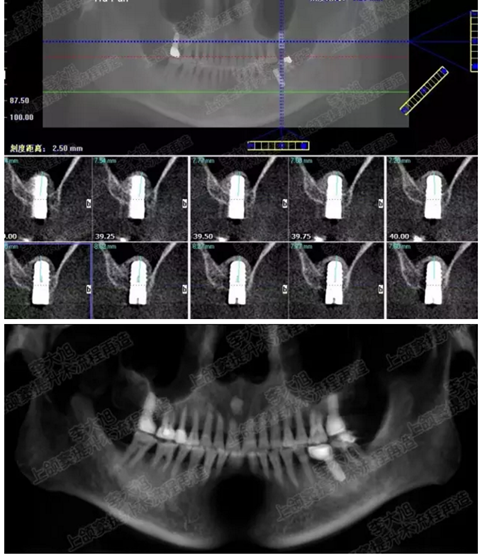

病例四

剩余骨量2mm-5mm且存在斜形竇底

007.png

提升8mm

008.png

009.png

病例五

剩余不足1mm

112.png

提升10mm

113.png